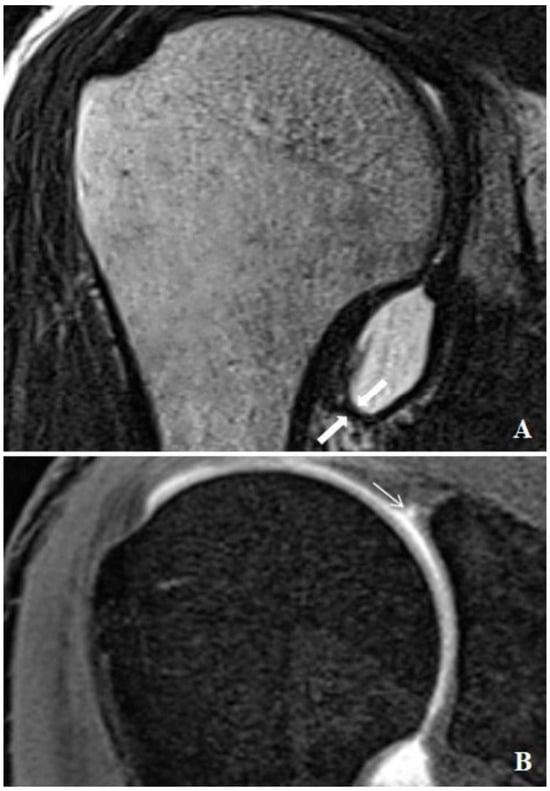

Relationship between SLAP Lesions and Shoulder Joint Capsule Thickness: An MR Arthrographic Study

2.2. Injection Technique, MR Arthrograms and Image Analysis